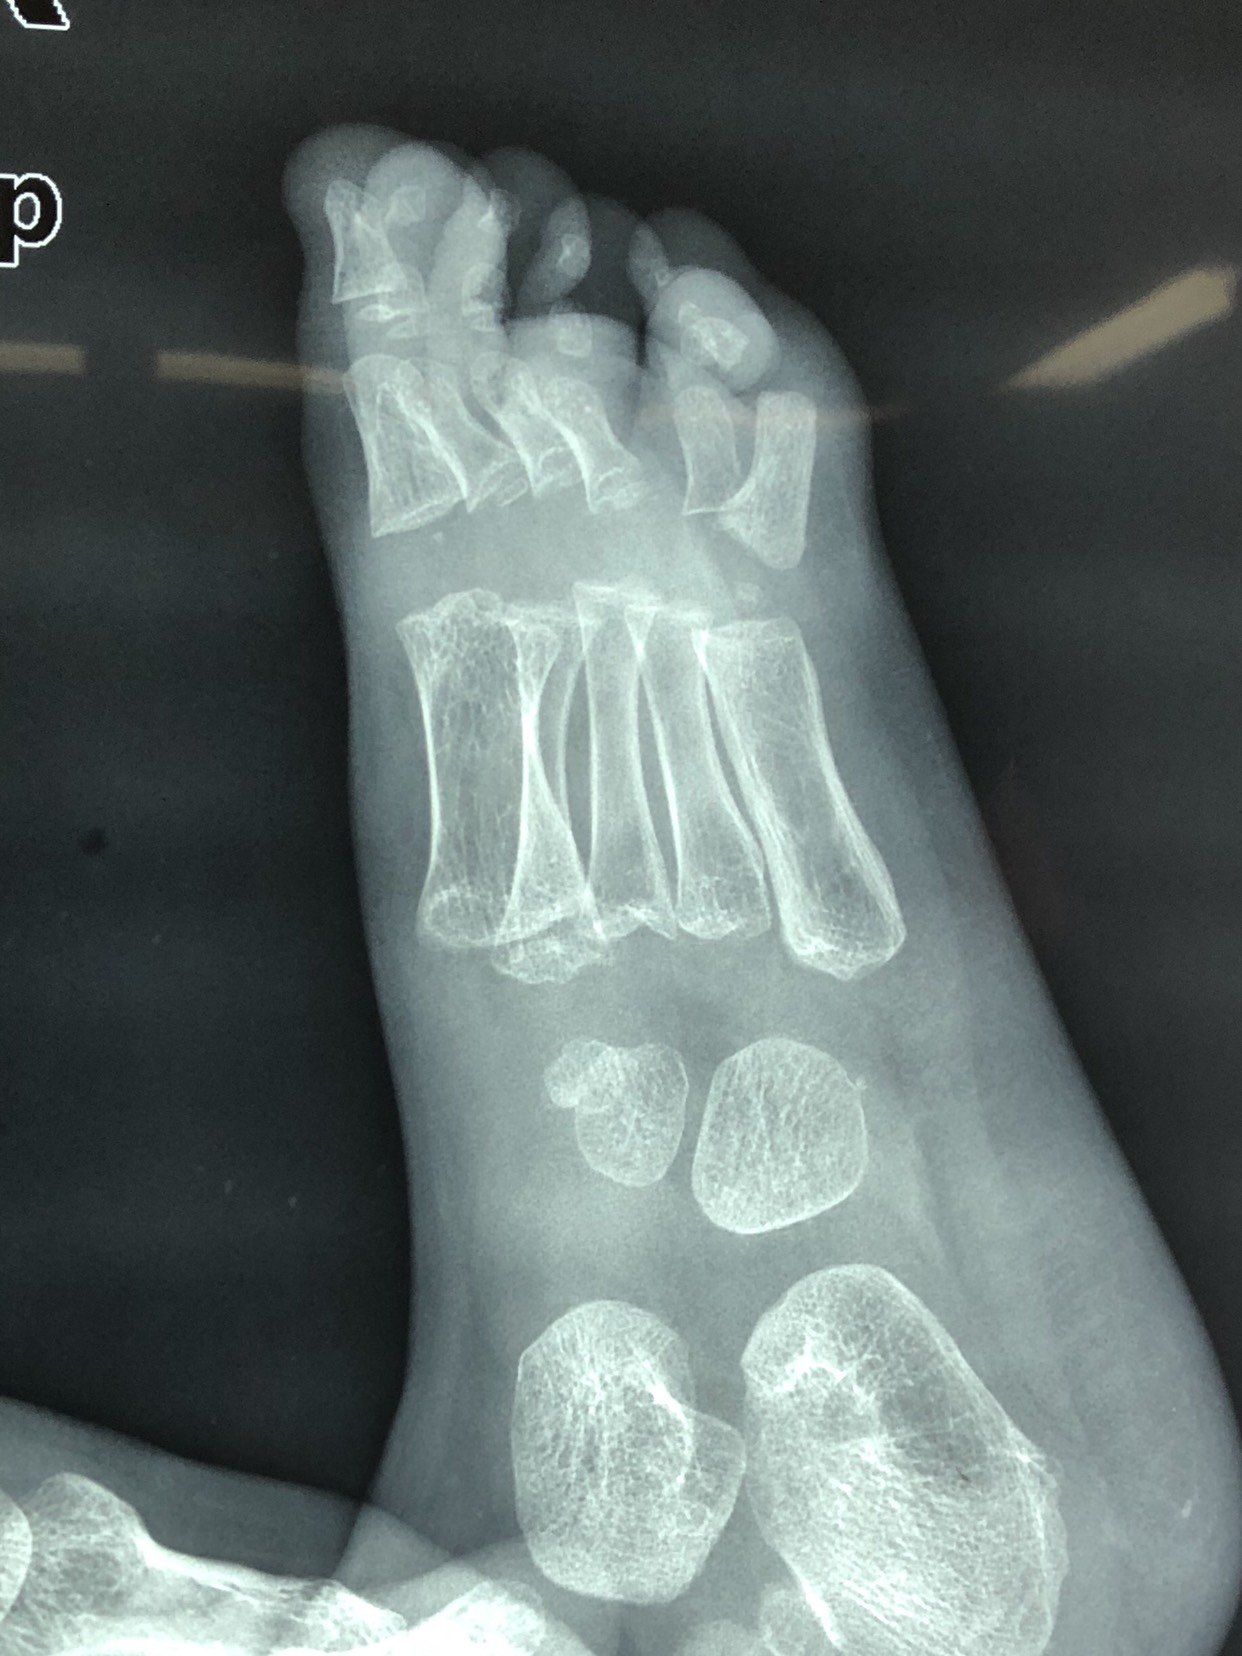

足趾畸形一例,如何诊断?

足趾畸形